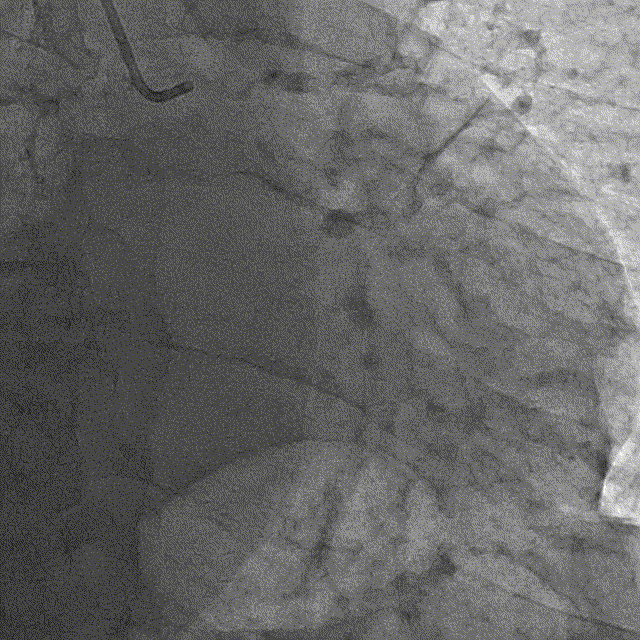

冠脉造影

冠脉造影结果:LM外膜钙化,内膜不光滑,中段狭窄90%,TIMI3级。LCX外膜钙化,内膜不光滑,TIMI3级。RCA外膜钙化,内膜不光滑,近段狭窄80%,中段狭窄90%,可见破损斑块,TIMI3级。

冠脉内介入治疗